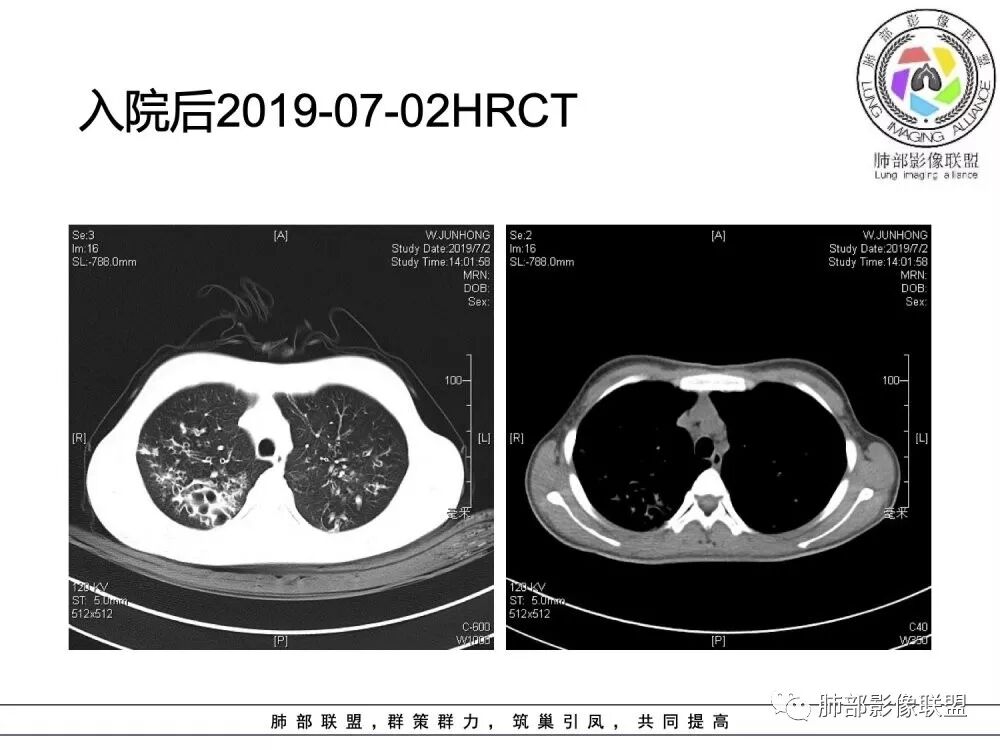

南边老师分析

这个病人15岁,病史10年,一直诊断支扩并感染,但是没提鼻窦病变;广泛支气管扩张,周围有伴随病灶,部分有钙化灶,肺气肿背景,首先是气道来源的病变,表现为:支气管壁增厚、支气管扩张、肺部感染;

(1)支气管壁增厚、支气管扩张

可广泛分布于两肺各叶,尤其是两肺上叶多见。支气管扩张主要是轻、中度柱状支气管扩张。支气管壁增厚既可发生于扩张的支气管,也可发生于非扩张的支气管,常为轻度增厚,管壁内外比较光滑。

(3)支气管黏液栓

由于黏液分泌物潴留在气管内形成,依据黏液存留的支气管走向不同而形态各异,多呈圆形、椭圆形、管状或尖端指向肺门的“V”形或“Y”形高密度阴影,密度均匀,边缘光滑锐利,CT值一般为15±10HU,但存留较久的黏液栓CT值可高达40~80HU,增强扫描无强化。

(5)斑片状阴影

表现为感染性支气管肺炎和亚段肺不张。呈1~3cm大小不等的斑片状高密度影,上肺野常见或上肺野病灶分布较多。